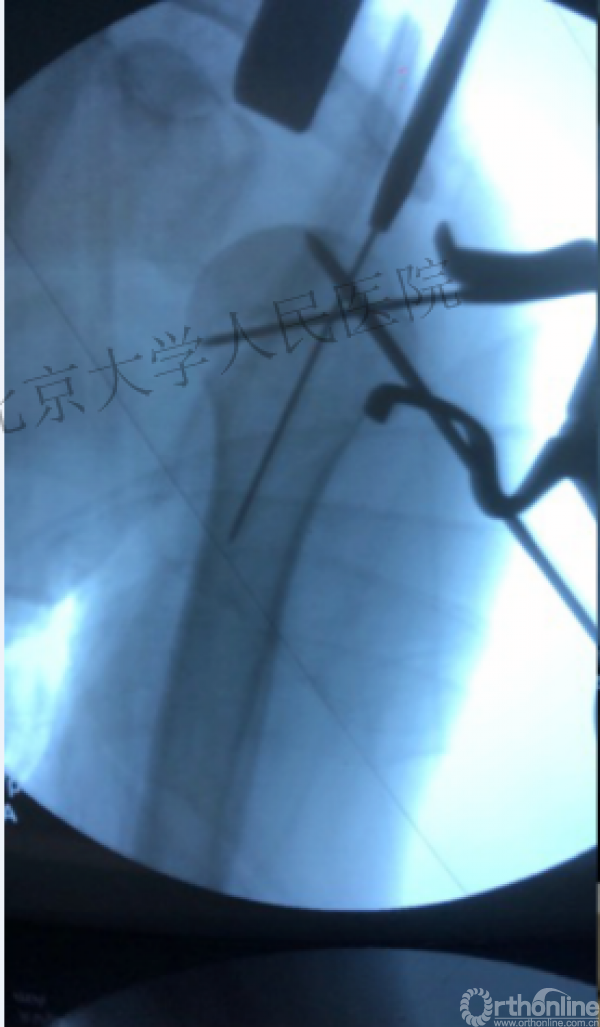

术中片

简单骨折的闭合复位技术:以克氏针作为“joystick”

克氏针的应用“joystick”

髓内钉的应用复位是关键